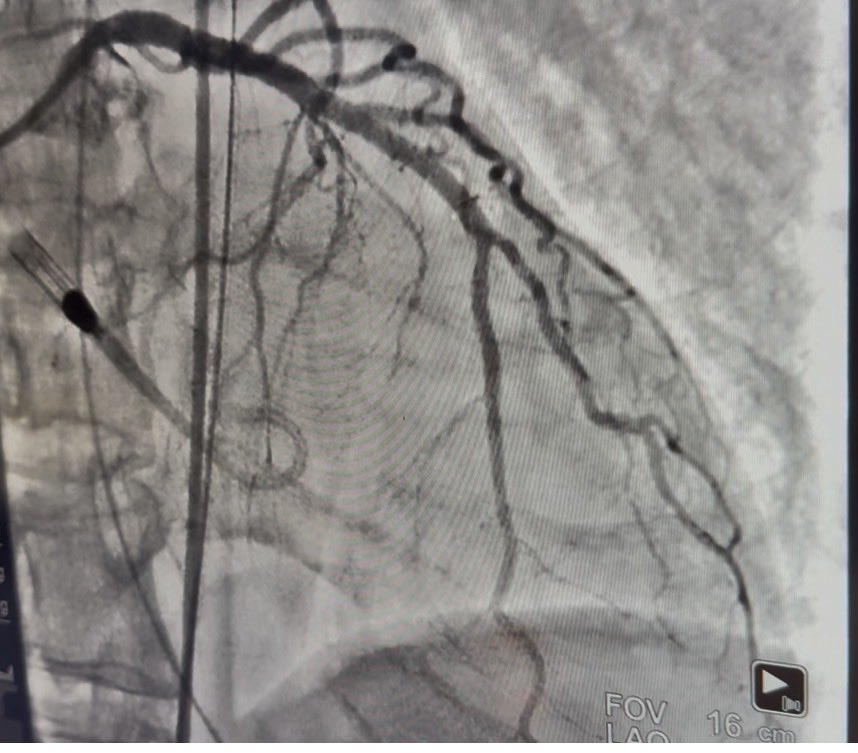

🫀 100 Lives, One Mission: Strengthening Heart Attack Care in Ethiopia! We proudly celebrate the 100th STEMI procedure at Heart Attack Ethiopia 🎉, a milestone achieved through the skill, dedication, and leadership of our local cardiologists, nurses and hospital staffs. This

🫀 100 Lives, One Mission: Strengthening Heart Attack Care in Ethiopia!

We proudly celebrate the 100th STEMI procedure at Heart Attack Ethiopia 🎉, a milestone achieved through the skill, dedication, and leadership of our local cardiologists, nurses and hospital staffs.